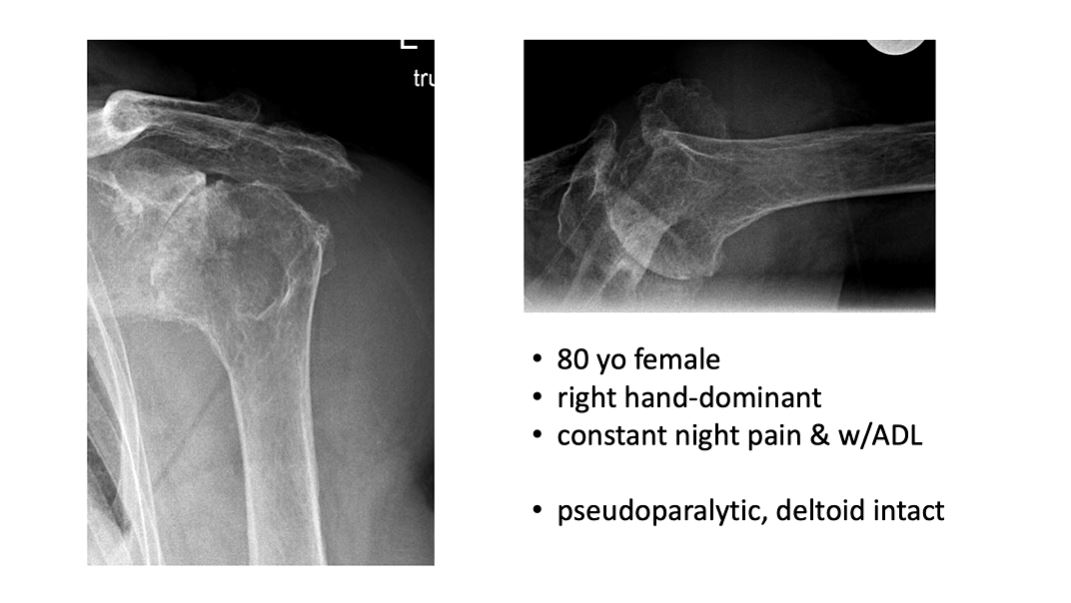

Research enthusiasts watch out! We are excited to present our Winglet Journal Club partner edition in cooperation with Enovis, focusing on the publication "Clinical and Radiologic Outcomes of Lima ProMade Custom 3D-Printed Glenoid Components in Primary and Revision Reverse Total Shoulder Arthroplasty with Severe Glenoid Bone Loss" (Rashid et al., 2023).

Episode #022 | Are Custom Components in RTSA Improving Patients' Outcomes?